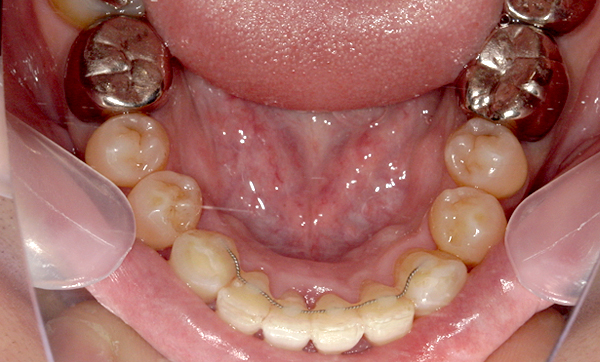

症例_009 「上下の前歯」症例

治療期間:7ヶ月金額:54万円+税20代女性捻転歯一部の反対咬合前歯のガタガタ

Before | After |

---|---|